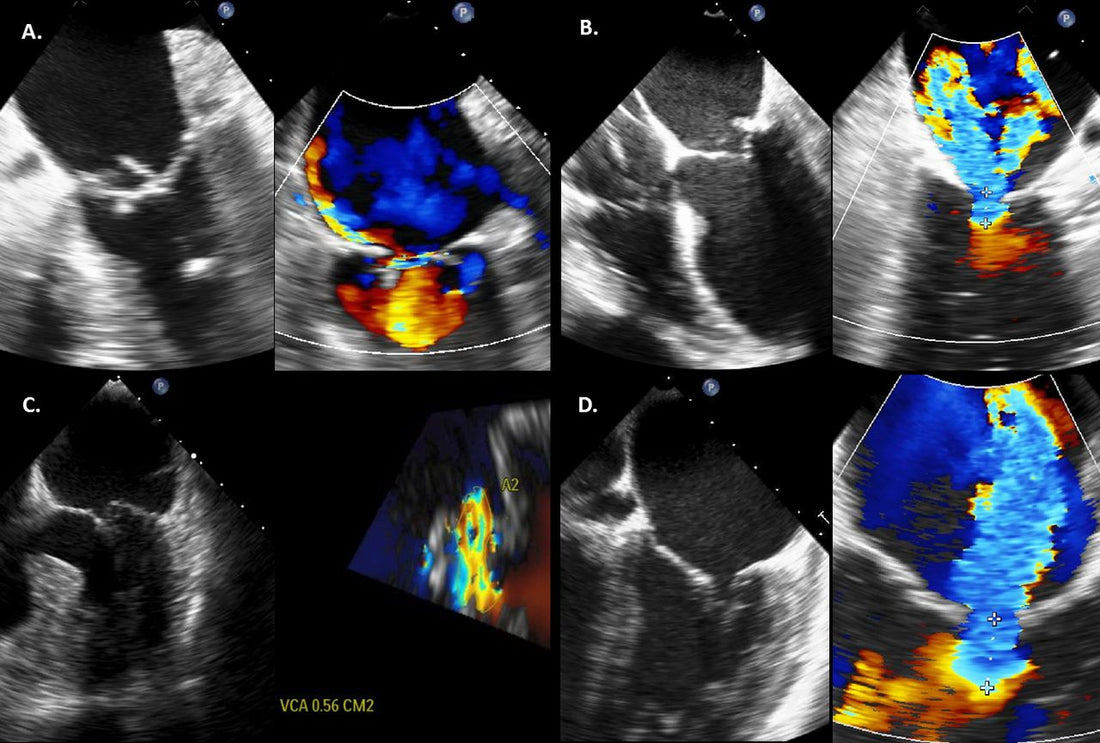

Regurgitasi aorta dapat didiagnosis melalui kombinasi evaluasi riwayat kesehatan, pemeriksaan fisik, dan tes diagnostik. Tes-tes ini mungkin termasuk ekokardiografi, elektrokardiogram (EKG), rontgen dada, dan MRI jantung. Tes-tes ini membantu menentukan tingkat keparahan kondisi dan memandu rencana perawatan.